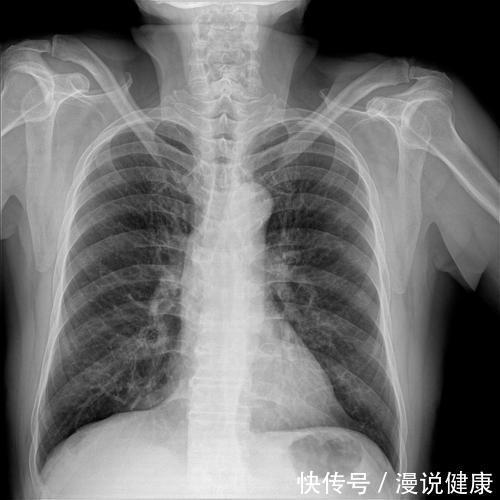

1、环境因素

长期生活在污染严重的环境当中,就很容易导致人身体发作肺癌。例如大气污染、装修建材、有害气体污染以及二手烟污染等。

其中大气污染当中含有PM2.5,也就是人们常说的入肺颗粒物,其中具备大量的有害物质和致癌物质,能够直接被肺泡组织所吸收,长时间吸入自然会增加肺癌的发病率。